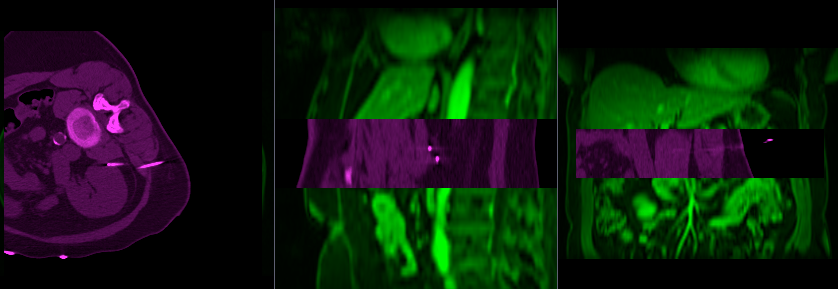

File:RegLib C17 unregistered.gif

Size of this preview: 800 × 276 pixels. Other resolutions: 320 × 110 pixels | 838 × 289 pixels.

Original file (838 × 289 pixels, file size: 232 KB, MIME type: image/gif, looped, 2 frames, 1.0 s)